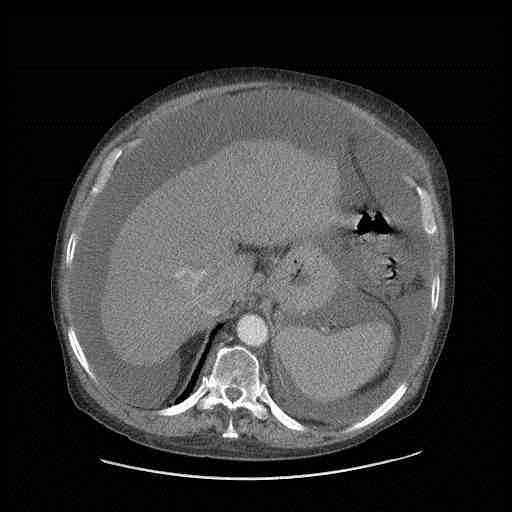

Niealkoholowe stłuszczeniowe zapalenie wątroby (nonalcoholic steatohepatitis – NASH), które jest postacią niealkoholowej stłuszczeniowej choroby wątroby (nonalcoholic fatty liver disease – NAFLD) jest jedną z częstszych chorób w krajach wysokorozwiniętych. Jak pokazują badania obserwacyjne, u około 20% chorych z NASH, w ciągu 10 lat może dojść do rozwoju marskości wątroby.

Istnieją nowe możliwości nieinwazyjnej diagnostyki dokonanej marskości. Wciąż nie dysponujemy jednak metodami, które pozwoliłyby śledzić lub umożliwiłyby monitorować postęp włóknienia wątroby w przebiegu NASH na wcześniejszych etapach choroby. W kilku badaniach wykazano, że jednym z teoretycznych markerów włóknienia w alkoholowej chorobie wątroby (alcoholic liver disease – ALD) może być immunoglobulina IgA w surowicy. Istnieje aktualnie pogląd, że ALD jest chorobą IgA-zależną. Jako, że istnieje szereg podobieństw w zakresie zmian histologicznych i odnośnie naturalnej historii ALD i NAFLD, wydaje się zasadne poszukiwanie odpowiedzi na pytanie czy podobnej relacji – między stężeniem IgA a progresją NAFLD – nie stwierdza się w NAFLD. Taki jest też temat ciekawej pracy zamieszczonej na łamach jednego z tegorocznych wydać Digestive Diseases and Sciences.